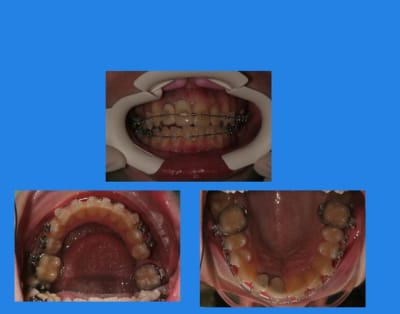

13/03/2010 à 23h42

contrôle 3 semaines après

13/03/2010 à 23h44

Puis elle ne vient pas pendant plus de 2 mois

et, oh surprise (mauvaise)

c’est la cata !!!

4 pzmuzx - Eugenol

Images 1 qtgoxf - Eugenol